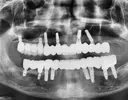

Implant tedavisi